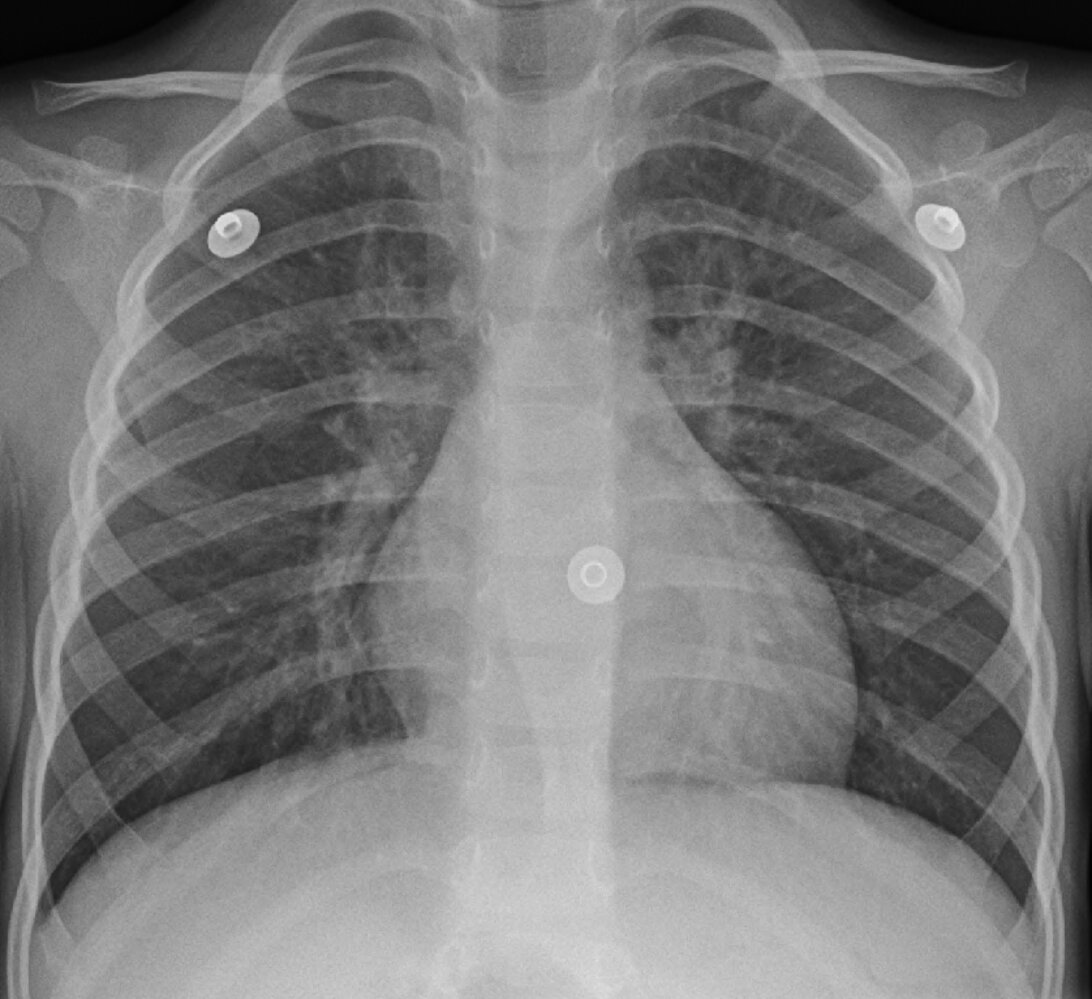

• Chest x-ray

• Indication: to evaluate for pneumonia in patients with abnormal examination findings or atypical clinical presentation [8]

• Findings: often normal or nonspecific, e.g., peribronchial thickening [11][12]